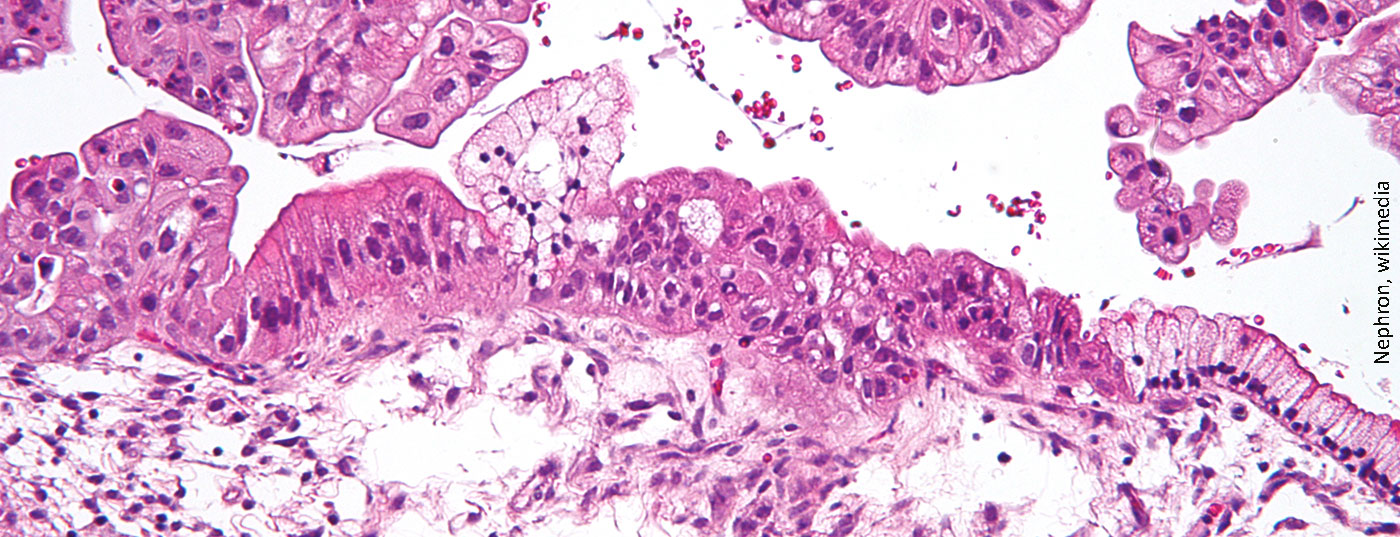

Erhaltungstherapie beim Ovarialkarzinom: Überlegungen in Zeiten von COVID-19

Krebspatienten gelten in der Corona-Pandemie als Risikogruppe. Doch bedeutet dies, dass man nun auf bestimmte Behandlungen verzichten sollte? Prof. Dr. med. Viola Heinzelmann-Schwarz, Gynäkologisches Tumorzentrum, Universitätsspital Basel, erläutert im Interview, was es angesichts der aktuellen Situation bei Patientinnen unter Erhaltungstherapie nach Ovarialkarzinom zu beachten gibt.